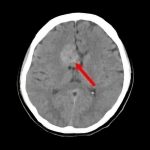

症例 '16年10月

No.

年_番号

手術年月

患者年齢

’16_145

'16年10月

40代

病名

術式

備考

脳室上衣腫

断層撮影

手術前

1

手術前2

手術後